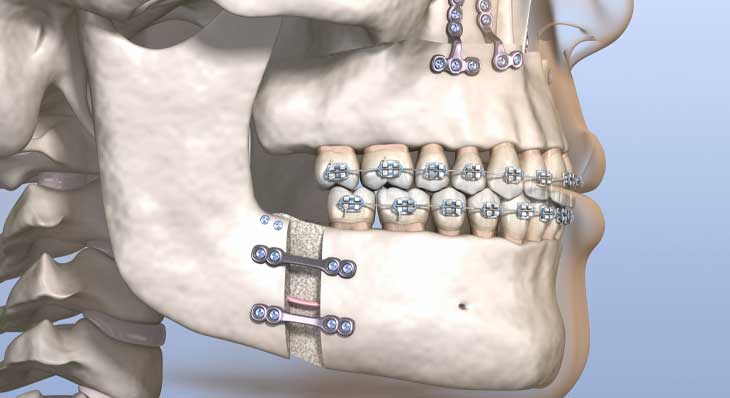

◦ انجام جراحی: جراحی در بیمارستان و تحت بیهوشی کامل انجام می شود. جراح با ایجاد برش هایی از داخل دهان، استخوان های فک را جابجا کرده و در موقعیت جدید با صفحات و پیچ های کوچک تیتانیومی ثابت می کند.